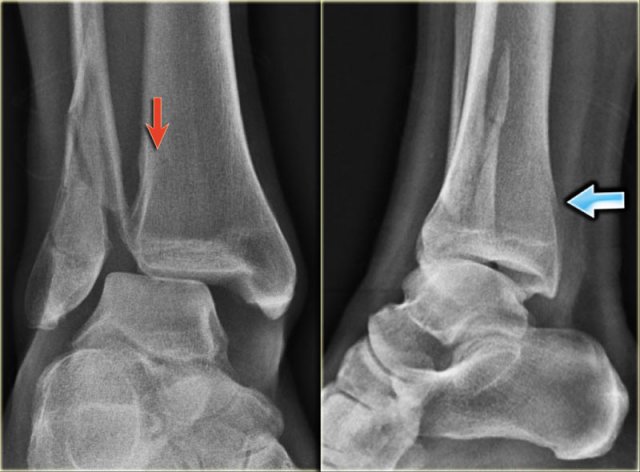

Weber-A stage I Weber-A stage I

Stage 1

The images show the usual Weber type A fractures.

These are all stage-1 fractures.

Stage-2 is extremely uncommon.

Notice the horizontal orientation of the fracture lines.

These are pull off type fractures as a result of avulsion.